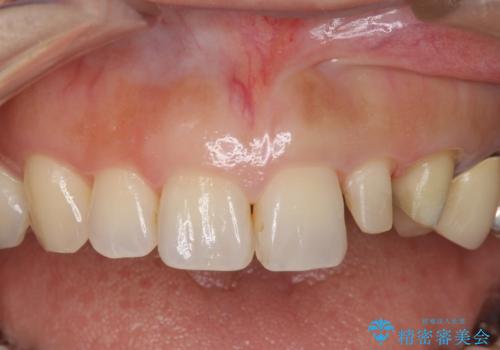

前歯が左右対称じゃない 保険の被せ物をきれいにしたい ホワイトニング併用

- 左上の前歯が小さく左右対称ではないのと、保険の前歯の被せ物のやりかえを希望して来院。

小さい前歯は、反対側と合わせた形にしました。

被せ物だけやりかえており、患者様のご希望もあり、根の治療や土台(コア)のやりかえは行なっていません。

左右対称に仕上げることができ、治療には非常に満足していただきました。